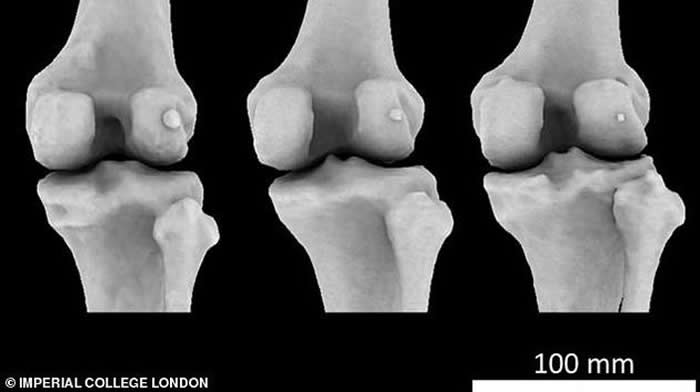

豆骨(fabella),是位于膝盖后方肌腱中的一块小骨骼,目前它在人体存在的概率是100年前的3倍,全球五分之二居民都长有豆骨。

豆骨(fabella),是位于膝盖后方肌腱中的一块小骨骼,目前它在人体存在的概率是100年前的3倍,全球五分之二居民都长有豆骨。它的直径不足1.3厘米,是在我们灵长类祖先身体上发现的,它被称为“骨骼阑尾”,因为它的存在是毫无意义的。

现今人类比过去更高、体重更大,因此膝盖后面的腓肠肌更大,这将形成压力和摩擦力。豆骨存在于连接肌肉和大腿骨的肌腱中,通过为肌腱提供一个光滑表面滑动来消除部分压力,当然,狗、猫和一些灵长目动物都具有这种豆骨。

豆骨也被称为籽骨,这是由于它生长在肌腱之中。膝盖骨是人体最大的籽骨,研究发现骨关节炎和神秘豆骨的存在具有直接联系,膝关节炎患者长有豆骨的概率是非骨关节炎患者概率的两倍。但是研究人员表示,目前还无法断定豆骨的存在导致了骨关节炎。人们还认为,令人讨厌的豆骨会影响膝关节置换手术,并且会导致身体不适感。